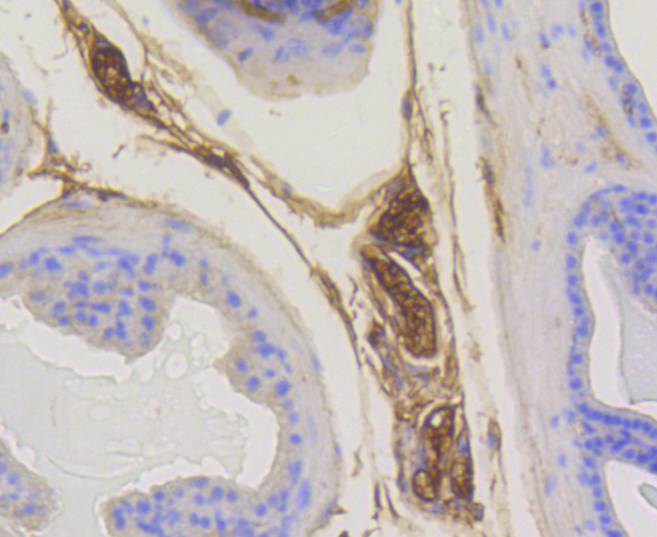

- 抗体名:

Rab5 Rabbit mAb

- 应用范围:

WB, IHC

WB: 1:1,000

IHC:1:50-1:200